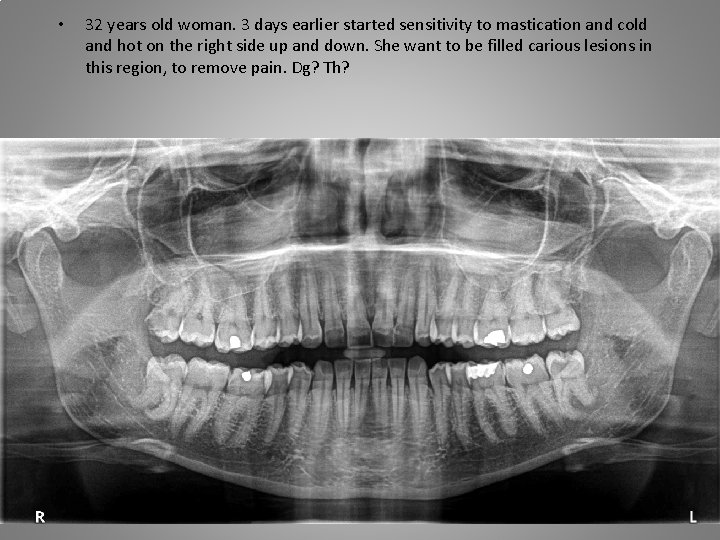

• 32 years old woman. 3 days earlier started sensitivity to mastication and cold and hot on the right side up and down. She want to be filled carious lesions in this region, to remove pain. Dg? Th?